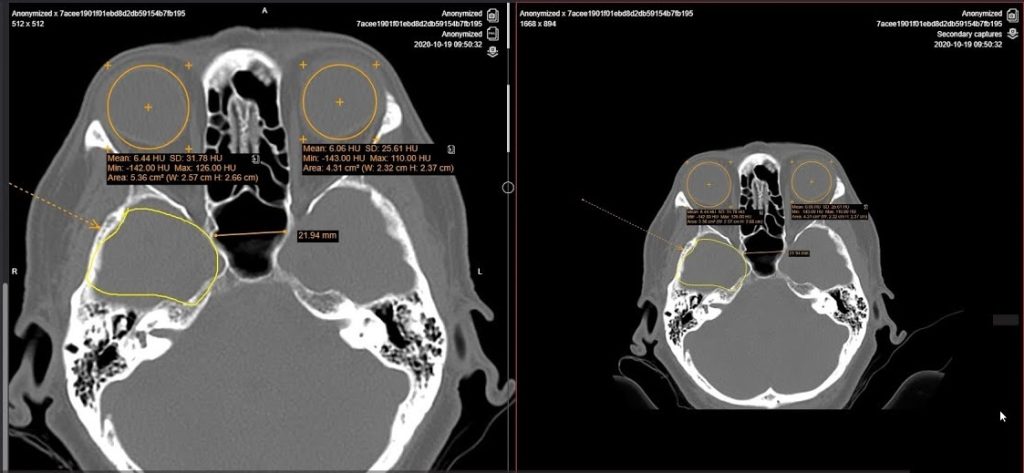

- Multi-Frame Images: Serangkaian gambar yang terkait dan diambil dalam satu waktu disimpan sebagai serangkaian frame dalam satu file DICOM. Contohnya termasuk serangkaian potongan gambar dari CT scan atau MRI, yang mewakili potongan yang diambil sepanjang sumbu tertentu dari tubuh pasien.

- Secondary Capture Images: Gambar-gambar ini adalah representasi digital dari gambar-gambar medis yang dihasilkan dari perangkat berbeda, seperti gambar dari layar monitor ultrasonografi atau foto radiografi digital. Mereka sering digunakan untuk dokumentasi, presentasi, atau tujuan referensi.